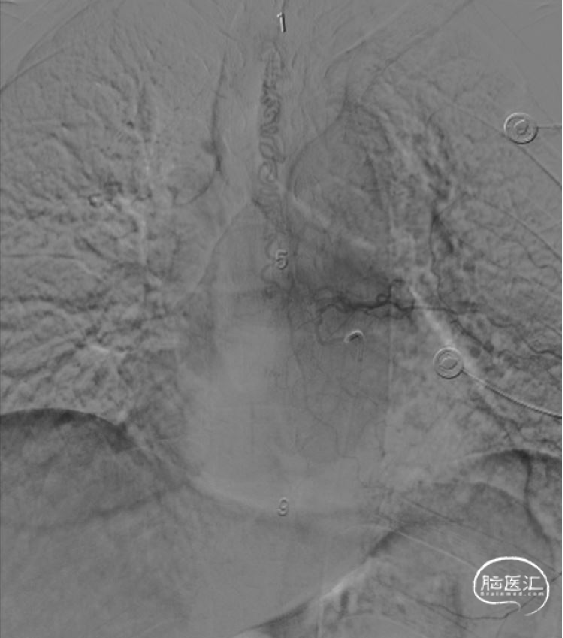

现病史摘要:缘于5月余前患者无明显诱因逐渐出现双下肢无力,走路时酸胀感,易疲劳,不能长距离行走,右下肢明显,晨轻暮重,无疼痛、肌肉萎缩和大小便异常,完善颈胸部MRI显示胸髓表面多发迂曲血管影,胸5-12椎体水平髓内异常信号。

术前影像(2024-02-06, 省二院)

image.png